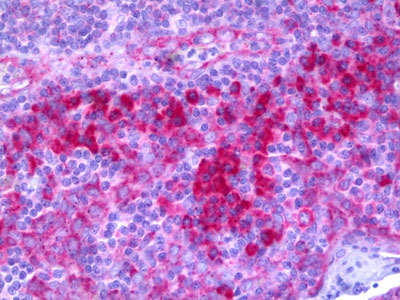

Images |

Western blot of extracts from 293/A549 cells, treated with etoposide 25 uM 1h, using APR02812G.

Anti-C1R / Complement C1r antibody IHC of human tonsil. |